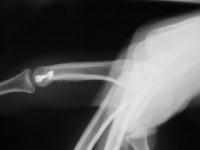

Unicondylar fractures of the phalangeal head are common, frequently unstable and unacceptably displaced. Although some may be treated successfully with percutaneous reduction and fixation, many require open reduction. In these cases, the screws were put right through the collateral ligament and sunk into the cortex. I think the simplest way to do this is to reduce and stabilize with two K wires, then remove the wires and replace with screws, one at a time, so reduction is maintained throughout. 1mm=39/1000" Kwire, so doing the math, here is how you choose the right sized Kwire to use as both drill and provisional fixation:

With two screws, bicortical fixation is not needed. The video below illustrates the steps involved, which are the same with either open or percutaneous fixation.